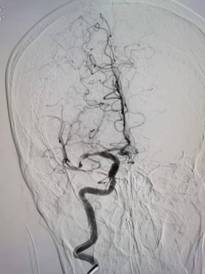

次日下午7点余,急促的电话铃声再次响起,患者80岁男性,发作性左侧肢体无力13天余,外院药物治疗症状仍有波动,住院总周青青医师评估病情后急诊完善多模磁共振检查,提示颅内大血管狭窄,介入团队宋文锋医师、李艳波医师等接到通知后,迅速赶到医院,披上铅衣,把患者推往介入手术室,迅速开通血管,术后患者肢体活动好转。然而,战斗还没有结束,端午节当日,值班医师刘洁查房时发现一位住院患者病情突然变化,随即仔细查体,核对病例后确定患者脑梗死加重,紧急行磁共振评估,发现患者梗死较前扩大,右侧大脑中动脉狭窄,通知介入团队刘福德医师、李艳波医师等迅速赶到医院。通过右侧大脑中动脉球囊扩张及支架植入术,堵塞的血流迅速恢复,麻醉醒后患者症状较前好转。手术还未结束,当地医院转来54岁男性患者,醒后卒中,当地医院磁共振发现右侧大脑中动脉狭窄,左侧肢体无力,跟家属沟通后急诊上台,行右侧大脑中动脉抽栓及支架植入术,术后患者肌力明显好转,又改变了一个患者的命运,挽救了一个家庭。